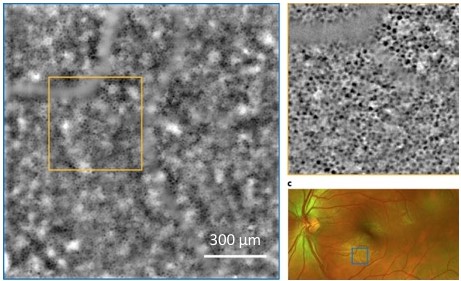

Kowalczuk L., Dornier R., Navarro A., Jeunet F., Moser C., Behar-Cohen F., Mantel I., Adaptive Optics-Transscleral Flood Illumination Imaging of Retinal Pigment Epithelium in Dry Age-Related Macular Degeneration, Cells (2025), 14(9), 633. doi: 10.3390/cells14090633. |

Govindahari V., Dornier R., Ferdowsi S., Moser C., Mantel I., Behar-Cohen F., Kowalczuk L., High-Resolution Adaptive Optics-Trans-scleral Flood Illumination (AO-TFI) Imaging of Retinal Pigment Epithelium (RPE) in Central Serous Chorioretinopathy (CSCR), Scientific Reports, 14.1 (2024):13689. doi: 10.1038/s41598-024-64524-4. |

Kowalczuk L., Dornier R., Kunzi M., Iskandar A., Misutkova Z., Gryczka A., Navarro A., Jeunet F., Mantel I., Behar-Cohen F., Laforest T., Moser C., in vivo Retinal Pigment Epithelium Imaging using Transscleral OPtical Imaging in healthy eyes, Ophthalmology Science, 100234 (2022). |

dos Santos F., Laforest T., Künzi M., Kowalczuk L., Behar-Cohen F., and Moser C., Fully automated detection, segmentation, and analysis of in vivo RPE single cells, Eye, June 2020. |

Laforest T., Künzi M., Kowalczuk L., Carpentras D., Behar-Cohen F. and Moser C. , Transscleral optical phase imaging of the human retina, Nature Photonics, March 2020. |